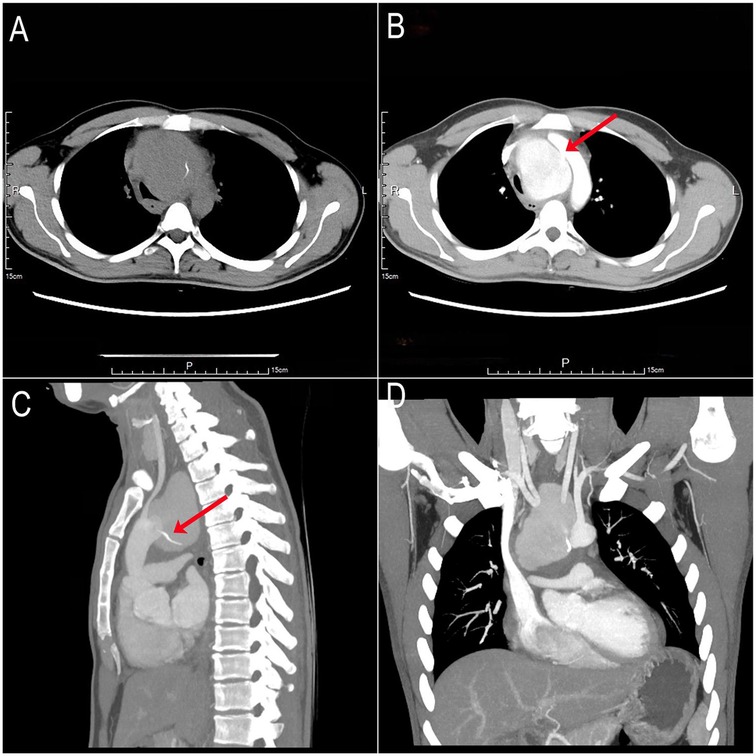

A 32-year-old male presented with cough and chest pain exacerbated by swallowing. Twenty days prior, he had accidentally ingested a fish bone but deferred medical evaluation. He subsequently developed high fever, worsening chest pain, and severe coughing. The patient had no significant past medical history and no family history of similar disorders or premature cardiovascular disease. On auscultation, lung fields were clear bilaterally, without rales or rhonchi. Heart sounds were regular, with no pathological murmurs detected. Non-contrast computed tomography (CT) revealed a large mediastinal mass containing a high-density foreign body (Figure 1A). Contrast-enhanced CT demonstrated a giant aortic arch pseudoaneurysm causing significant tracheoesophageal compression and mediastinal shift to the right, along with the retained foreign body (Figure 1B) and a substantial filling defect in the posterior aortic arch wall (Figures 1C,D).

Figure 1. Preoperative non-contrast and contrast-enhanced CT scans. (A) Non-contrast CT: Giant mediastinal mass containing a hyperdense foreign body. (B) Contrast-enhanced CT: Giant aortic arch pseudoaneurysm (posterior wall) with a 1-cm filling defect (red arrow). (C,D) Contrast-enhanced CT: Foreign body tip penetrating toward the aortic arch (red arrow).